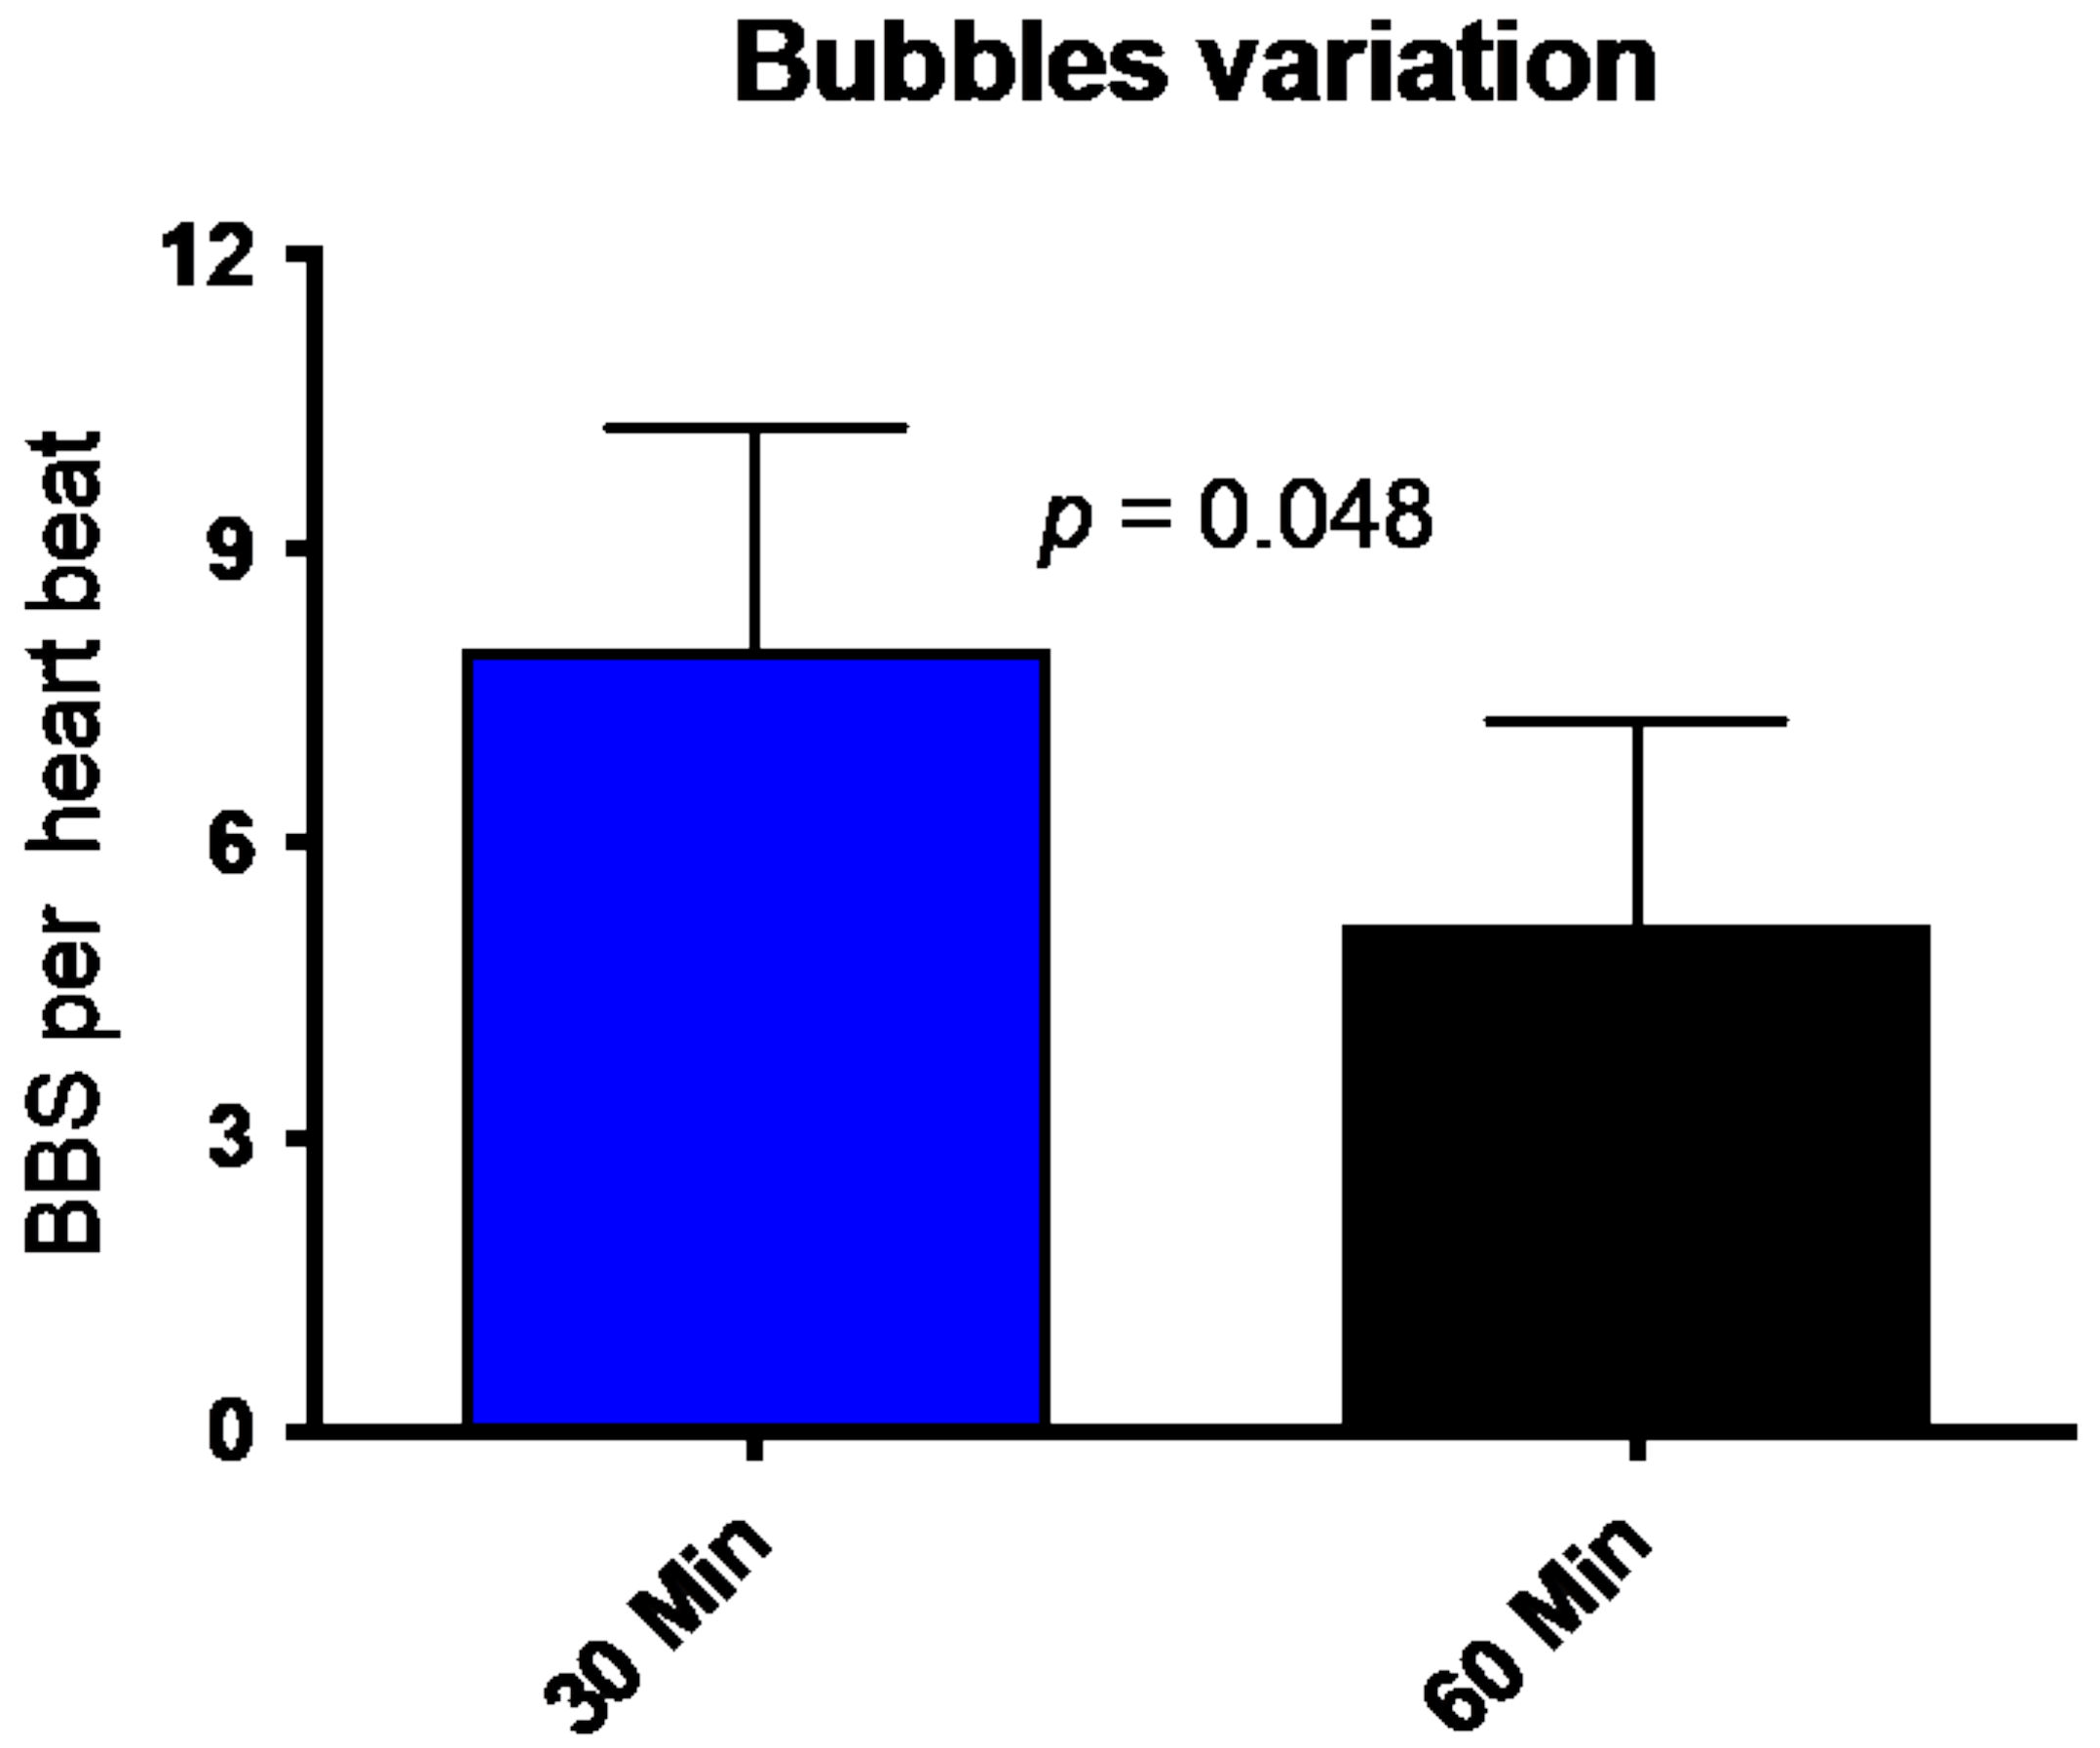

2.2.3. Post Diving Vascular Gas Emboli (VGE)

4.2. Diving Related

5.2. Flow-Mediated Dilation (FMD) and Vascular Gas Emboli

- Germonpré, P.; Papadopoulou, V.; Hemelryck, W.; Obeid, G.; Lafère, P.; Eckersley, R.J.; Tang, M.-X.; Balestra, C. The use of portable 2D echocardiography and ’frame-based’ bubble counting as a tool to evaluate diving decompression stress. Diving Hyperb. Med. J. 2014, 44, 5–13. [Google Scholar]

- Balestra, C.; Theunissen, S.; Papadopoulou, V.; Le Mener, C.; Germonpré, P.; Guerrero, F.; Lafère, P. Pre-dive Whole-Whole Body Vibration Better Reduces Decompression Induced Vascular Gas Emboli than Oxygenation or a Combination of Both. In Physiology in Extreme Conditions: Adaptation and Unexpected Reactions; Electronic Edition; Trivella, M.G., Capobianco, E., L’Abbate, A., Eds.; Frontiers Media: Lausnne, Switzerland, 2017. [Google Scholar]

- Imbert, J.-P.; Egi, S.M.; Germonpré, P.; Balestra, C. Static Metabolic Bubbles as Precursors of Vascular Gas Emboli During Divers’ Decompression: A Hypothesis Explaining Bubbling Variability. Front. Physiol. 2019, 10, 807. [Google Scholar] [CrossRef] [Green Version]